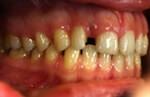

Patientin – 29 Jahre, Angle Kl. I, Invisalign für 9,5 Monate

Persistierender 52

(hier bereits entfernt)

12 war distal von 52 durchgebrochen

vorher

nachher